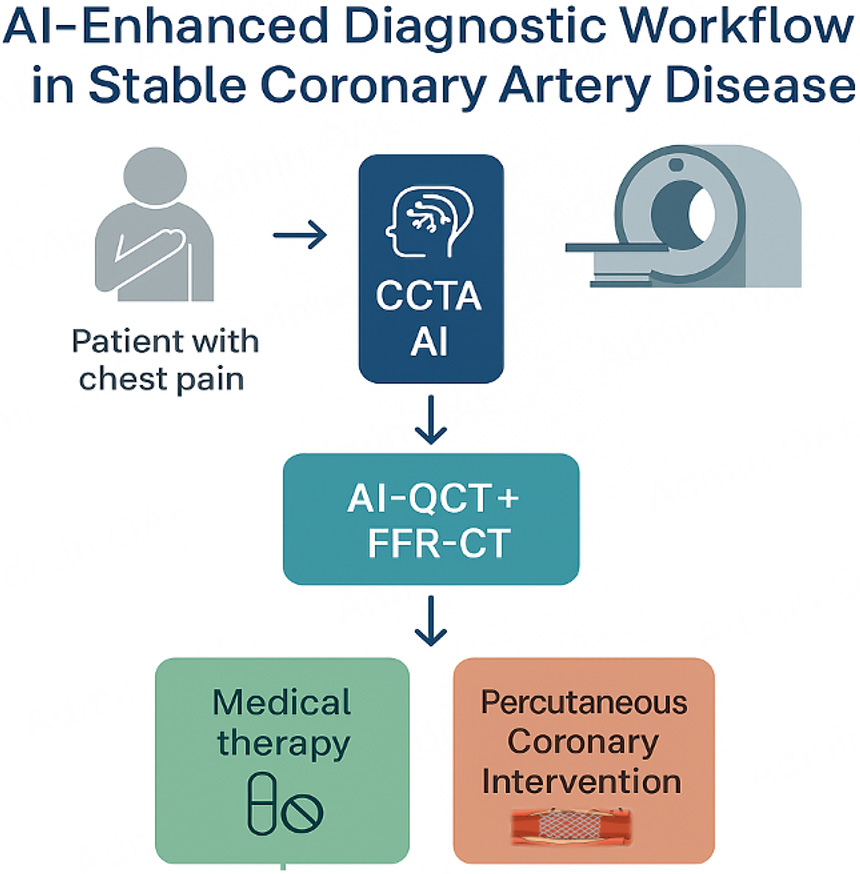

AI boosts precision in interventional cardiology but requires real-world validation. #ImagingAI #ClinicalAI #CardioInnovation @adrianocaixeta @drandrewsharp @rickytiago @DrSheilaSahni @TheNarulaSeries @MichaelMegalyMD @Pushpendraamu @JeremyKingPCI @alma_palau @kevinjamescroce

✨ AI in Interventional Cardiology 🤖 Improves imaging & plaque detection ⚙️ Aids planning, risk stratification 🌐 Needs validation & ethics #InterventionalCardiology #AI #PlaqueImaging 🔗 oaepublish.com/articles/2574-…